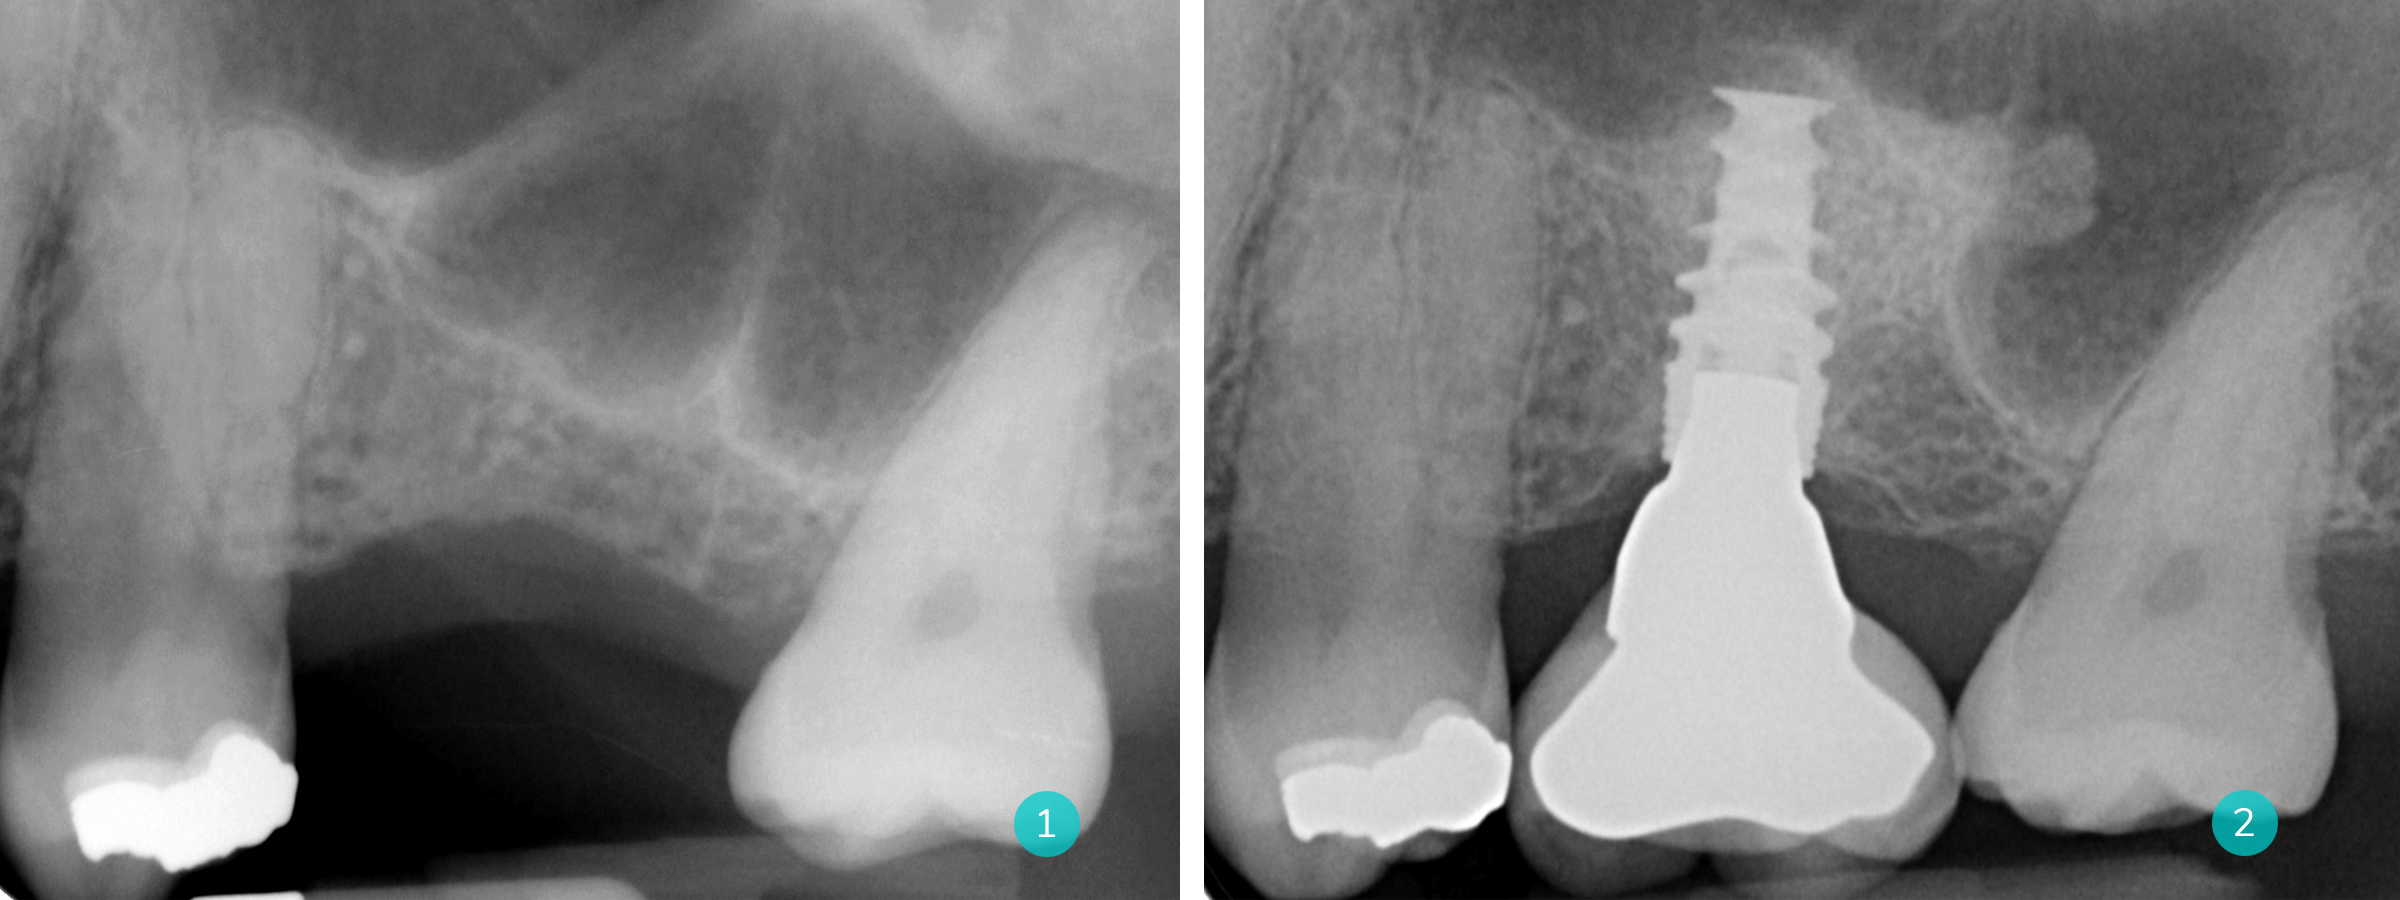

Het komt frequent voor dat de sinusbodem verder uitzakt na tandextractie waardoor er te weinig kaaksbot resteert om implantaten te plaatsen. Door een sinuslift kan dit verholpen worden. Via een opklap van het tandvlees en gebruik van een aantal boortjes wordt toegang gemaakt tot de zijkant van de sinus. Vervolgens wordt het intern vlies losgemaakt en opgetild. Kunstbot wordt tussen de sinusbodem en het opgetilde vlies geplaatst. Finaal wordt een zg. ´membraan´ aangebracht en wordt de wonde gesloten dmv meerdere hechtingen die na 2 weken worden verwijderd. Na een helingsperiode van 4 tot 6 maanden kunnen implantaten worden geplaatst.